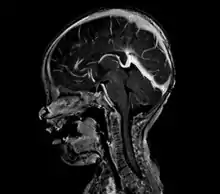

Large arteriovenous malformation of the parietal lobe

A cerebral AVM diagnosis is established by neuroimaging studies after a complete neurological and physical examination.[5][12] Three main techniques are used to visualize the brain and search for an AVM: computed tomography (CT), magnetic resonance imaging (MRI), and cerebral angiography.[12] A CT scan of the head is usually performed first when the subject is symptomatic. It can suggest the approximate site of the bleed.[3] MRI is more sensitive than CT in the diagnosis, and provides better information about the exact location of the malformation.[12] More detailed pictures of the tangle of blood vessels that compose an AVM can be obtained by using radioactive agents injected into the blood stream. If a CT is used in conjunction with an angiogram, this is called a computerized tomography angiogram; while, if MRI is used it is called magnetic resonance angiogram.[3][12] The best images of a cerebral AVM are obtained through cerebral angiography. This procedure involves using a catheter, threaded through an artery up to the head, to deliver a contrast agent into the AVM. As the contrast agent flows through the AVM structure, a sequence of X-ray images are obtained.[12]